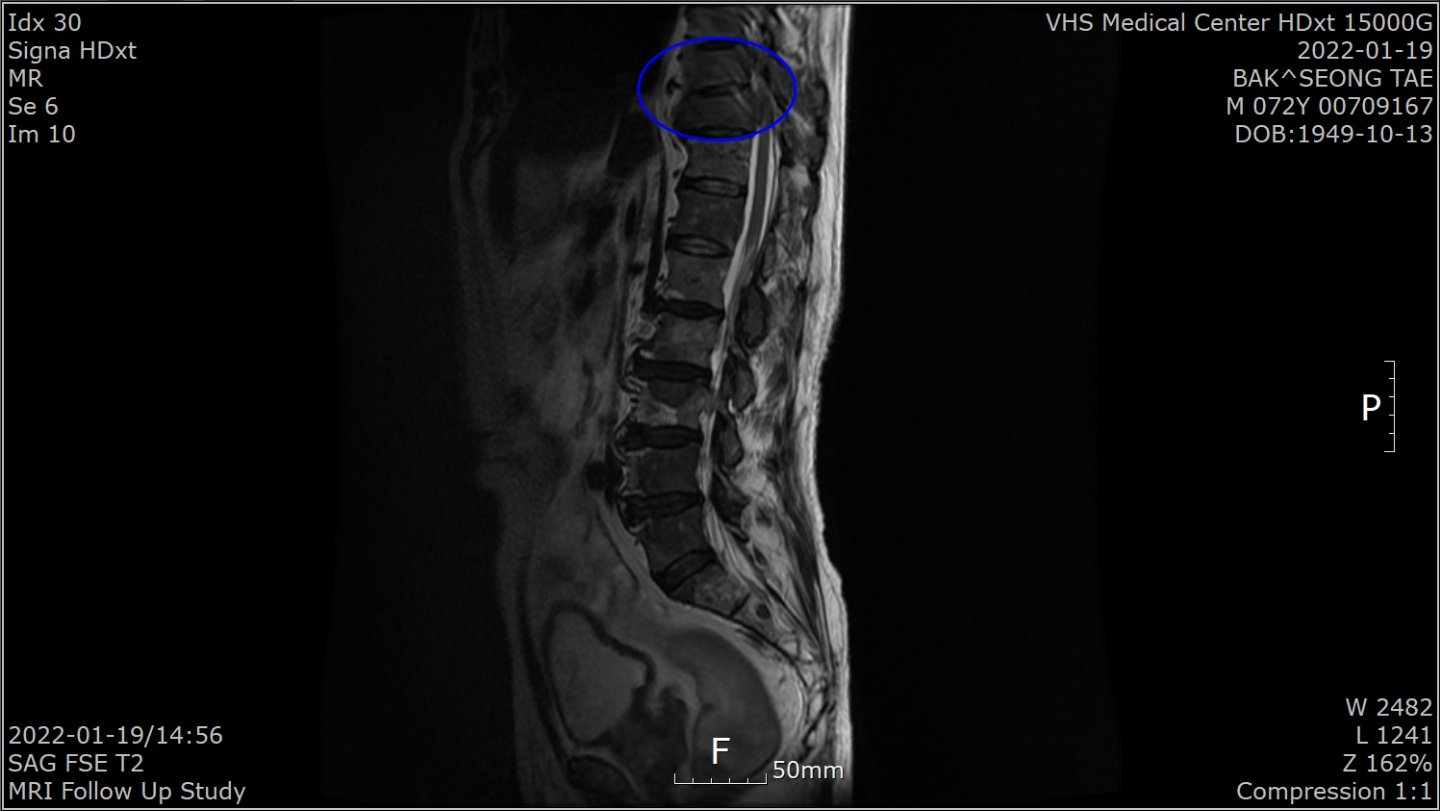

“1월 말 허리가 아파 병원에 갔더니 전립선암 말기라고 하더라고요. 전 베트남 참전용사로 국가유공자라 중앙보훈병원에서 진단 받았습니다. PSA(Prostate Specific Antigen·전립선 특이항원·전립선암의 선별검사 및 치료 판정을 위한 종양지표지자 검사)가 935 ng/mL라는 겁니다. PSA 4 ng/Ml 이하가 정상이라는데…. 너무 놀라서 그동안 아무 증상이 없었다고 했더니 전립선암은 증상이 없다 갑자기 나타난다고 하더군요. 전이가 돼 흉추 9, 10번이 시커멓게 썩었다고 하더군요. 참 나…. 방법이 죽을 방법 밖에 없다니. 하느님이 원망스러웠습니다.”

4월 29일 검사에서 PSA 수치가 0.059ng/mL로 떨어진 것이다. 그는 “MRI(자기공명촬영) 결과 새까맣던 흉추도 하얗게 정상으로 돌아왔다”고 했다. 말기암 판정 5개월여 뒤인 7월 29일 검사에선 PSA가 0.008 ng/mL로 떨어져 있었다.